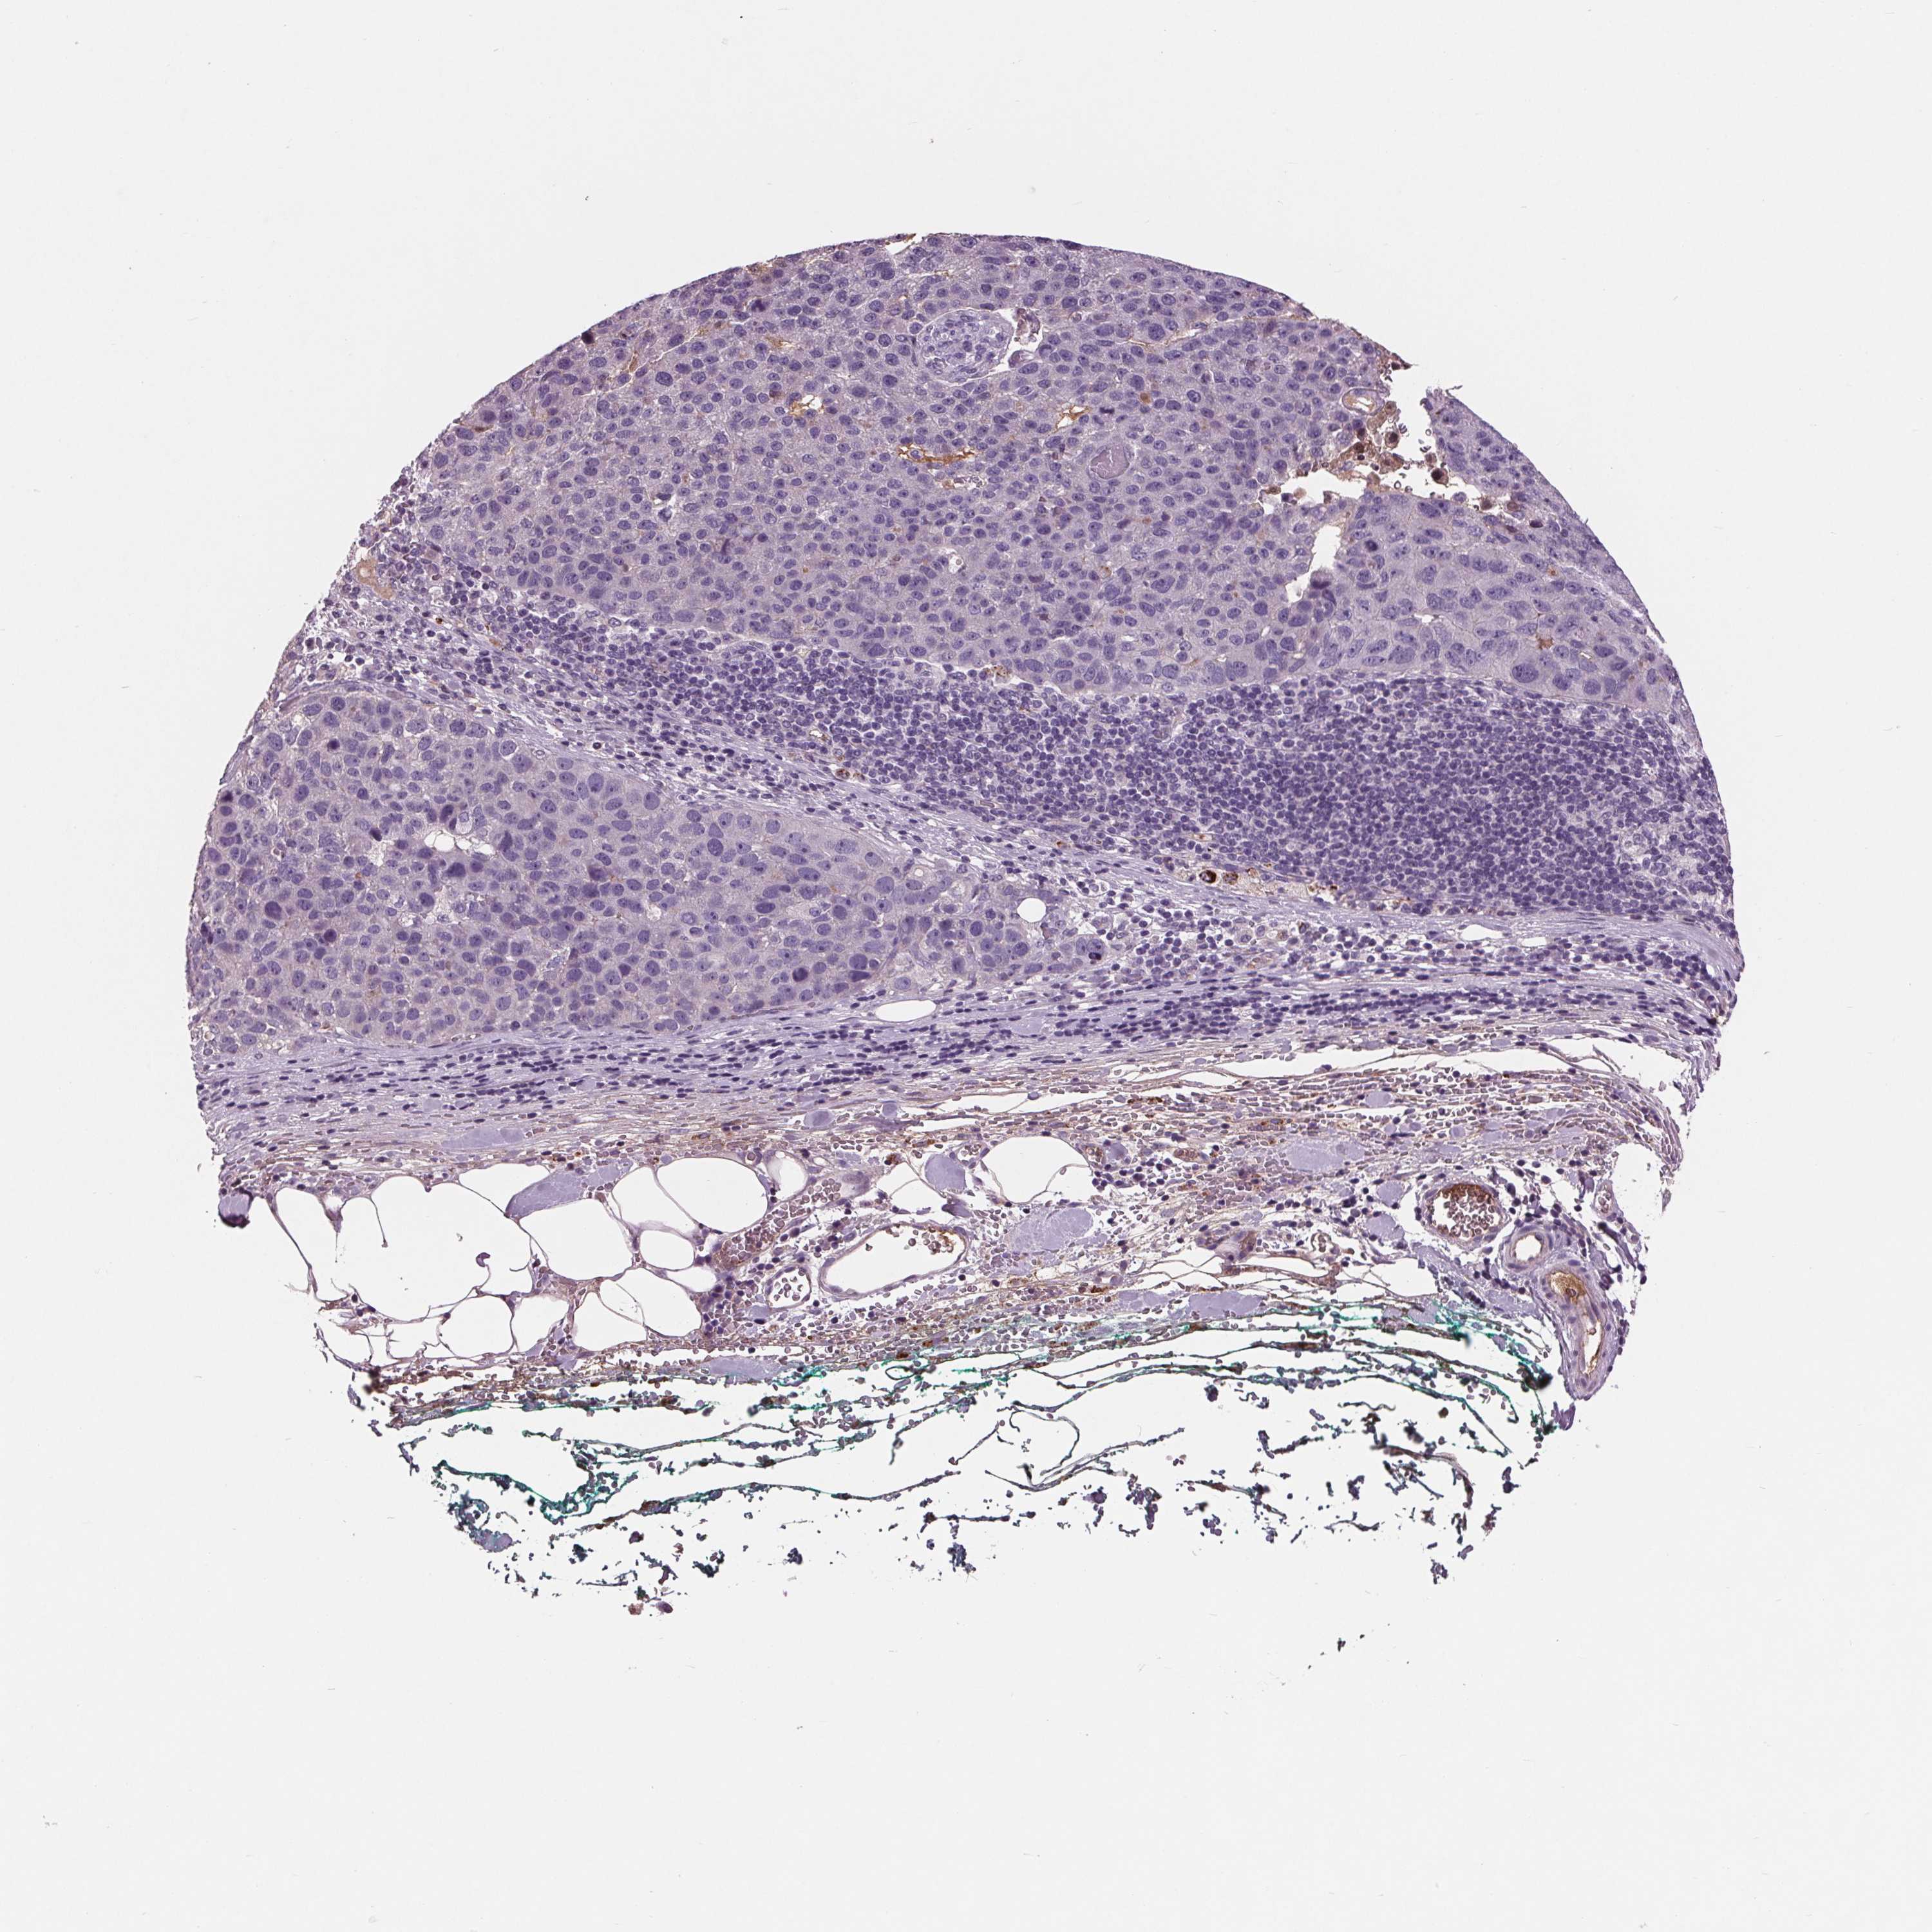

PANCREATIC CANCER - Protein expressioni

A mouse-over function shows sample information and annotation data. Click on an image to view it in a full screen mode. Samples can be filtered based on level of antibody staining by selecting one or several of the following categories: high, medium, low and not detected. The assay and annotation is described here.

Note that samples used for immunohistochemistry by the Human Protein Atlas do not correspond to samples in the TCGA dataset.

Antibody stainingi

Antibody staining in the annotated cell types in the current human tissue is reported as not detected, low, medium, or high, based on conventional immunohistochemistry profiling in selected tissues. This score is based on the combination of the staining intensity and fraction of stained cells.

Each image is clickable and will lead to virtual microscopy that enables deeper exploration of all samples and also displays staining intensity scores, fraction scores and subcellular localization as well as patient and tissue information for each sample.

Antibody HPA043823

Antibody CAB069427

Staining

High

Medium

Low

Not detected

Intensity

Strong

Moderate

Weak

Negative

Quantity

>75%

75%-25%

<25%

None

Location

Nuclear

Cytoplasmic/membranous

Cytoplasmic/membranous,nuclear

Adenocarcinoma, NOS